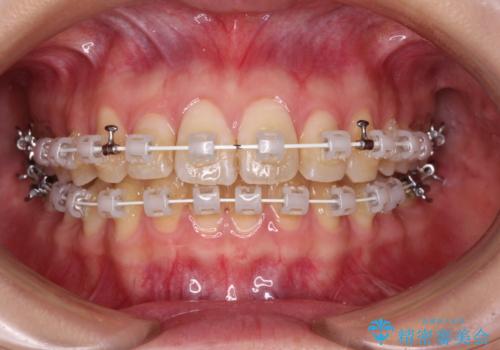

- 矯正装置

- 審美装置

- 1年5ヶ月

- 10-30回